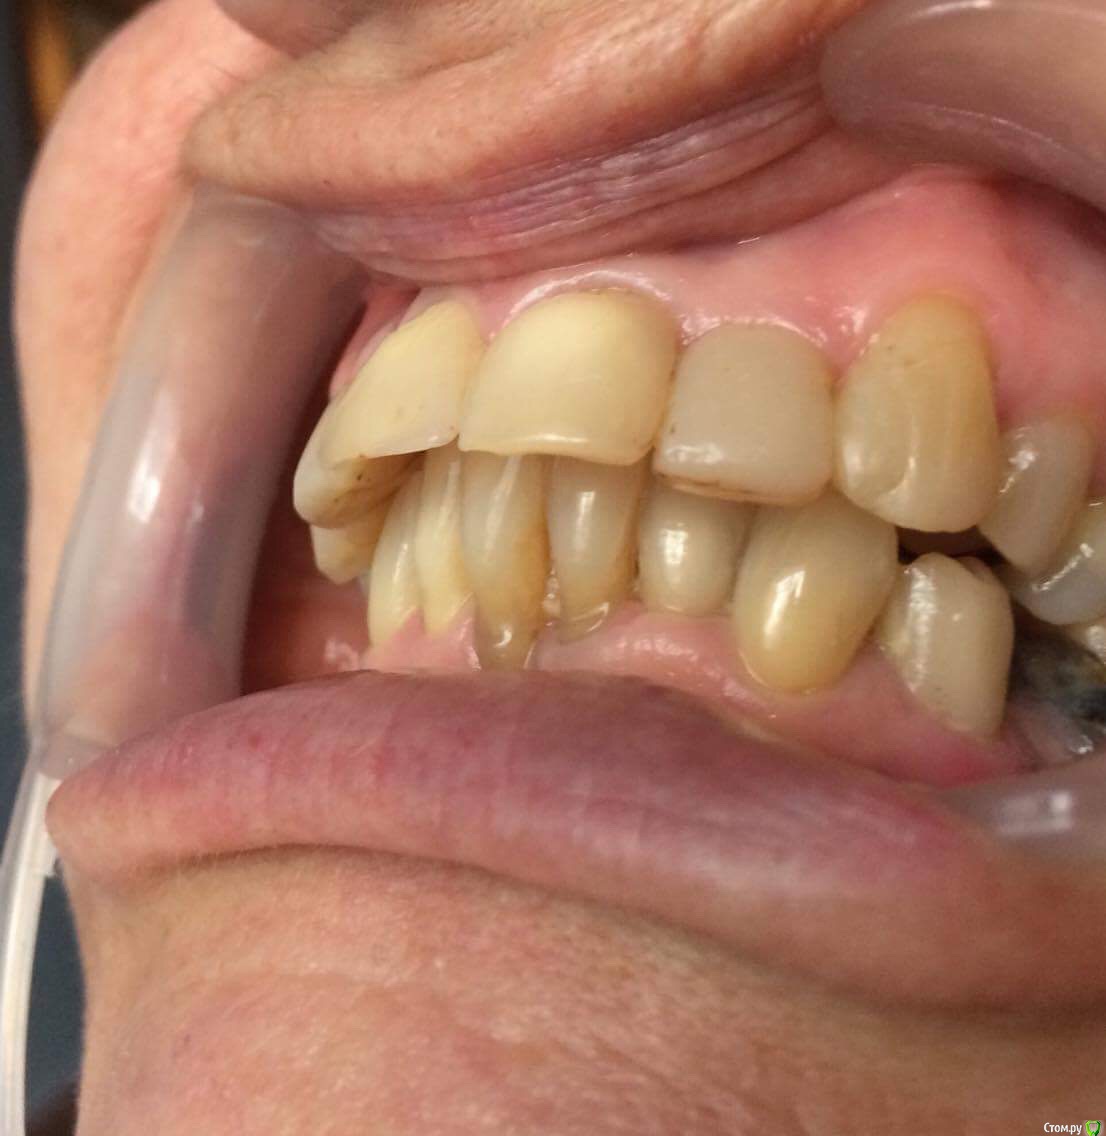

dr.Dre Опубликовано 27 июня, 2017 Поделиться Опубликовано 27 июня, 2017 Добрый день коллеги тему уже создавал но дал мало информации ,пациентка 58 лет .Помогите составить план лечения,имплантацию не потянет .Нужно ли здесь поднимать прикус? Ссылка на комментарий

chervoncevdaniil Опубликовано 27 июня, 2017 Поделиться Опубликовано 27 июня, 2017 (изменено) Ну в таком случае я не знаю как вы будете низ боковые сегменты протезировать,но 36 однозначно под удаление,26 и 27 в связи с деформацией плоскости видимо тоже придется,47 и 17 под вопросом и у нее получаются концевые дефекты.Опять же повторюсь,очень плохо видно что в боковом отделе,но настолько прикус вы навряд ли поднимете,чтобы и боковые зубы остались и при этом фронт не получился как у лошади,потому что по размерам резцы и клыки абсолютно нормальные Изменено 27 июня, 2017 пользователем chervoncevdaniil Ссылка на комментарий